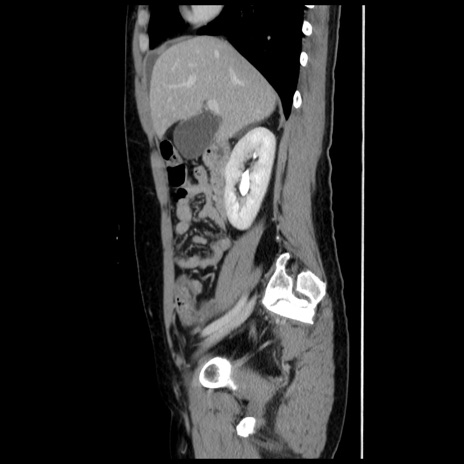

症例10(矢状断像)

【症例】 50歳代女性

【主訴】 腹痛

【現病歴】前日生レバーを食べた。今朝に排便あり。 昼前に突然発症の腹痛を生じ、当院救急外来を受診した。

【既往歴】 子宮筋腫にてで子宮全摘後

【身体所見】 意識清明、腹部:平坦、軟、下腹部やや左を中心に圧痛・反跳痛あり、筋性防御あり

【データ】WBC 7800、CRP 0.07